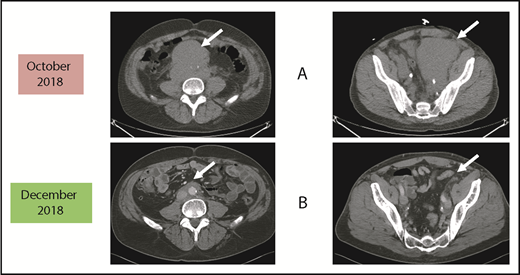

Before and after 3 months of acalabrutinib. A 54-year-old man was diagnosed with stage IVB MCL in 2014. He received chemoimmunotherapy including cytosine arabinoside and an adjuvant autologous SCT. (A) In 2018, he relapsed with left leg swelling due to bulky pelvic disease and a new deep vein thrombosis. (B) After biopsy proof of relapsed MCL, he received acalabrutinib 100 mg twice daily, rituximab, and apixaban; within 3 months, he achieved a marked response with no side effects of the combination. He has returned to full-time work and continues on therapy as of January 2019.

Patients who relapse are typically treated with salvage chemoimmunotherapy or other approved agents. These include the proteasome inhibitor bortezomib,13,14 the immunomodulatory agent lenalidomide,15-19 the mammalian target of rapamycin complex 1 inhibitor temsirolimus (Europe, not United States),20-24 and the Bruton tyrosine kinase (BTK) inhibitors discussed in the next section.25-29 The bcl-2 inhibitor venetoclax has orphan drug designation (but not approval) for MCL.30,31 Despite the plethora of agents for this disease, most patients will need all of them during their lifetime. Thus, there is always a need for additional agents as illustrated by the case described in Figure 1.

As reported in the clinical trial,43 acalabrutinib at the recommended dose of 100 mg twice daily is well-tolerated as demonstrated by only 1.6% of patients requiring dose reductions and only 6.5% of patients discontinuing acalabrutinib due to adverse events. Of note, atrial fibrillation was not observed in any patient. The most common side effects were headaches (36%) and diarrhea (38%), both of which were typically grades 1-2 and self-limited.43,44 If treatment of these is needed, then oral nonnarcotic agents that do not impair platelet function are recommended. These would include acetaminophen alone or with caffeine. Bleeding events were usually grade 1-2 and consisted of bruising and petechiae; there was 1 case of grade 3 gastrointestinal hemorrhage. Significant myelosuppression can occur and grade 4 neutropenia occurred in 6%. For these grade 3/4 toxicities, dose reductions to 100 mg daily may be required. It is not known what effect dose reduction has on tumor response. In patients such as the 1 described in Figure 1, acalabrutinib at full dose can be given with direct oral anticoagulants with appropriate instructions to watch for bleeding complications.